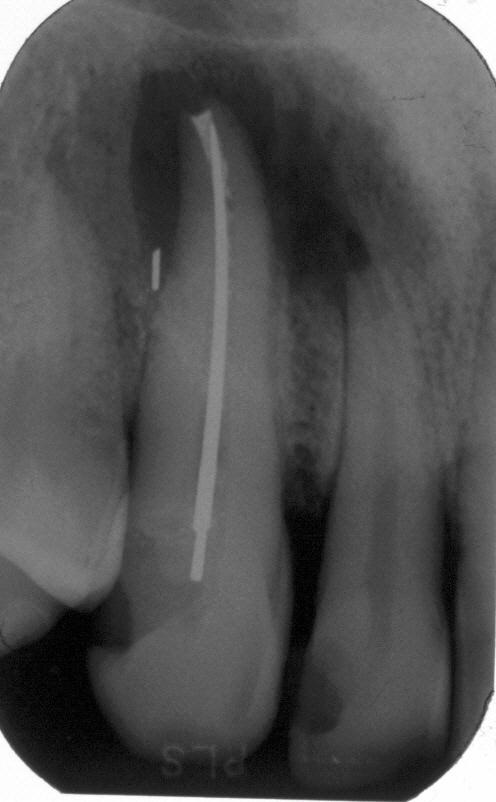

Röntgenologischer Ausgangsbefund im März 1996 bei Zahn 13 mit Silberstiftwurzelfüllung und chronisch apikaler Parodontitis; Zustand vor umfangreicher ZE-Neuversorgung. Erste Therapie der Wahl ist in diesem Fall immer die orthograde Revision

Wurzelfüllung im April 1996 in lateraler Kondensation mit normierter Guttapercha und AH 26